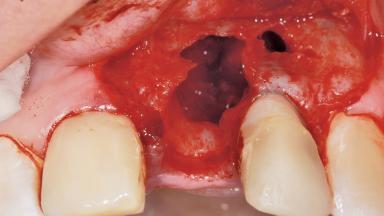

Late Placement of an Implant in a Maxillary Left Central Incisor Site

A 36-year-old female patient was referred for the replacement of the upper left central incisor (tooth 21), which had fractured. Although the tooth had been asymptomatic for many years, the crown began to loosen, at which time she presented to her dentist for an assessment. Teeth 21 and 22 had both been endodontically treated many years previously. She was a healthy individual and a non-smoker.

On examination, the patient had a low lip line and only displayed the coronal half of the anterior teeth when smiling.

The crown of tooth 21 was splinted to the adjacent teeth with composite resin, and the gingiva was inflamed.